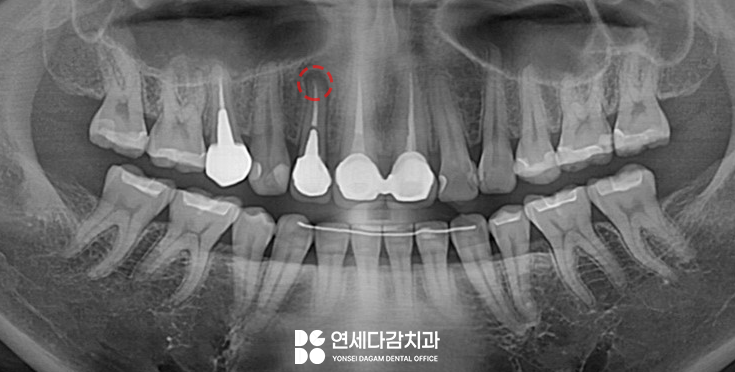

6개월 뒤 정기검진을 통해

가락동 치과 에서 파노라마

방사선 사진을 촬영하여 확인한 결과,

치근단 병소가 확연히 줄어든 것을

확인할 수 있었습니다.